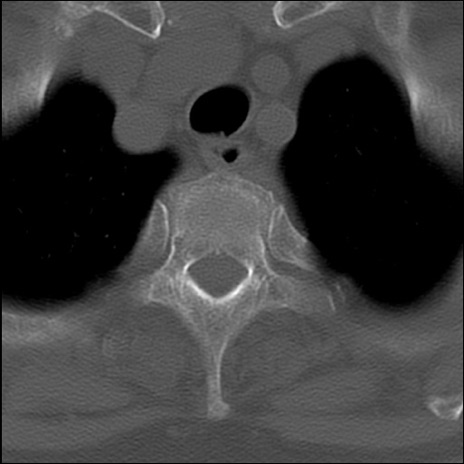

症例48 頚椎CT(横断像)

頚椎CT